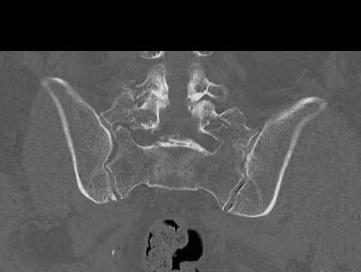

Sacral insufficiency fractures